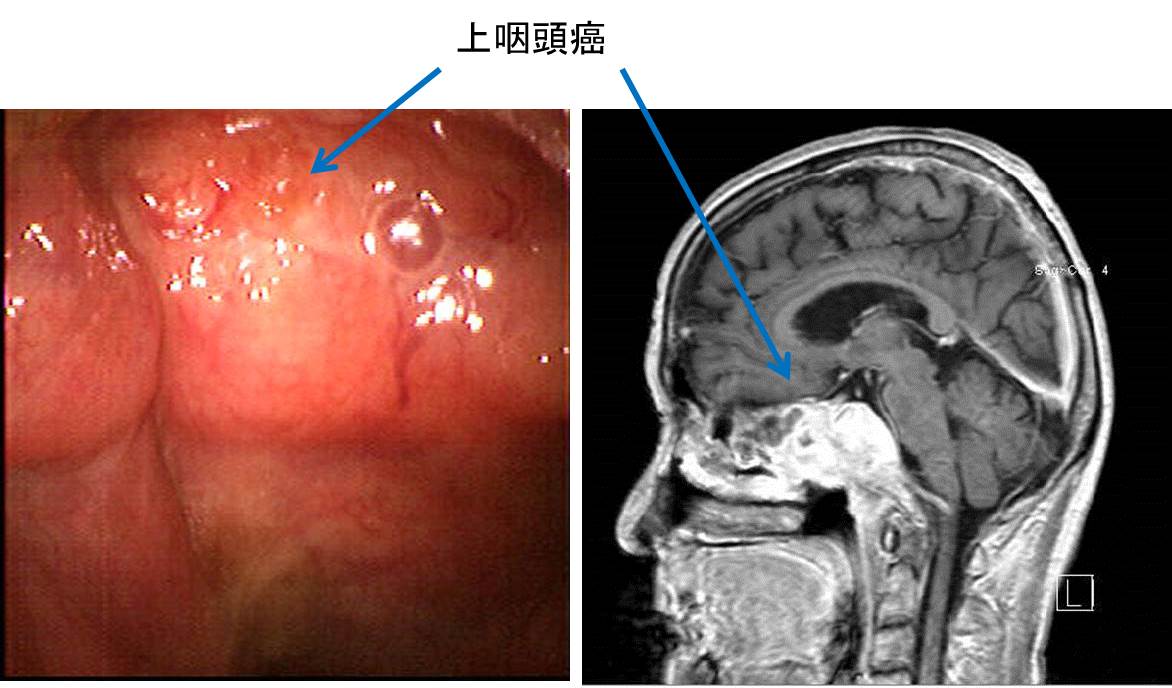

Ct検査よりがん組織と正常組織の区別が明確でct検査とは異なる情報からがんの深さや広がりリンパ節への転移の有無を調べます 7超音波エコー検査 首の表面から超音波をあ てそのはね返りをモニターで見ながら確認. 下咽頭癌の進展範囲を読影する際のチェックポイント 腫瘍の最大径 喉頭への進展の有無 軟骨浸潤の有無 上下方向への進展範囲の決定中咽頭頸部食道 軟部組織浸潤の有無特に梨状癌 梨状窩尖部への進展の有無.

中咽頭癌 ct. 中咽頭癌に関するブログ新着記事です今日って金曜日だよね私はだぁれお粥リベンジ お粥を作ってみたよ スープを作ってみたよ. Ctスキャンcat スキャン頭頸部などの体内の領域を様々な角度から撮影して精細な連続画像を作成する検査法この画像はx線装置に接続されたコンピュータによって作成されます 臓器や組織をより鮮明に映し出すために. 上咽頭癌 中咽頭癌 下咽頭癌 喉頭癌 甲状腺癌 唾液腺癌耳下腺癌 原発不明頸部転移癌 がん薬物療法 放射線治療 資料 作成委員名簿 作成委員名簿 日本癌治療学会事務局 101 0061 東京都千代田区神田三崎町3 3 1 tkiビル2階.

Chapter 2 頭頸部がんの検査と診断 頭頸部がん がん免疫 Jp Immuno

咽頭がんを早期発見するには そもそも咽頭とはどこのこと Helc